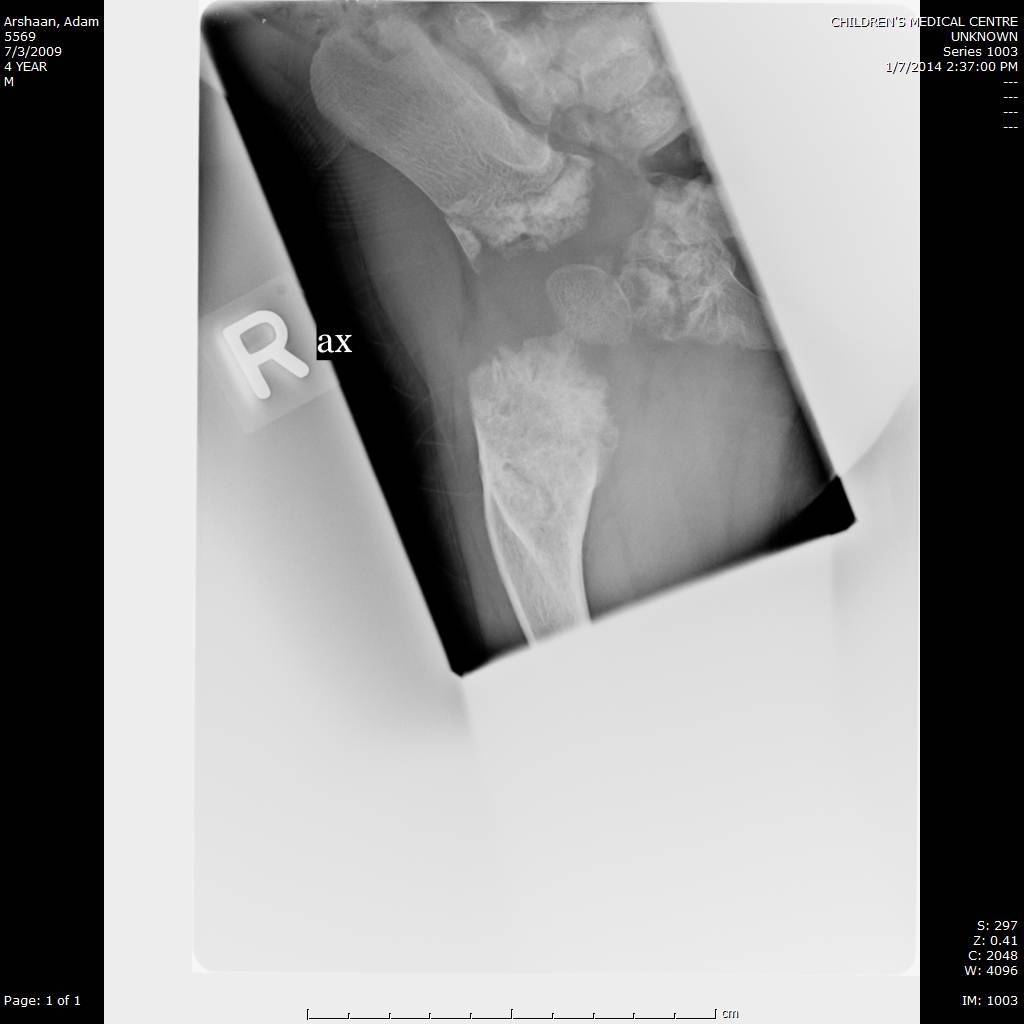

Here we share radiographic images to help with diagnosis of Jansen's disease:

Jansen's patients show extreme disorganization of the metaphyses of the long bones and of the metacarpal and metatarsal bones in sharp contrast to the almost normal appearance of the epiphyseal centers, which on x-ray appear widely separated from the long bones. The chin is receding. The fingers, especially the distal phalanges, are very short. The spine, pelvis, and lower legs are distorted.